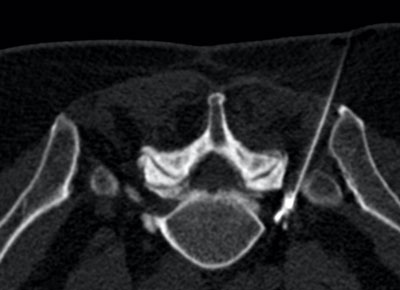

Bei der Periradikulären Therapie (PRT) werden die Medikamente direkt an die Austrittstelle der Nervenwurzel aus dem Wirbelkanal appliziert (Bild 1). Bei der Facettengelenksinfiltration werden die Medikamente exakt um die kleinen Wirbelgelenke gegeben, um hier die Schmerzen zu lindern.

Bild 1. Periradikuläre Therapie (PRT). Auf diesem Querschnitt durch den Körper sehen Sie zentral im Bild die Wirbelsäule und jeweils nach außen die Beckenknochen – der Knochen ist hell, die Weichteilstrukturen sind dunkel. Im Bild erkennen Sie von rechts oben eine Nadel, die exakt bis an die austretende Nervenwurzel der Patientin plaziert wurde. Das helle Kontrastmittel verteilt sich von der Nadelspitze genau um die Nervenwurzel und die Medikamente können hier einwirken.